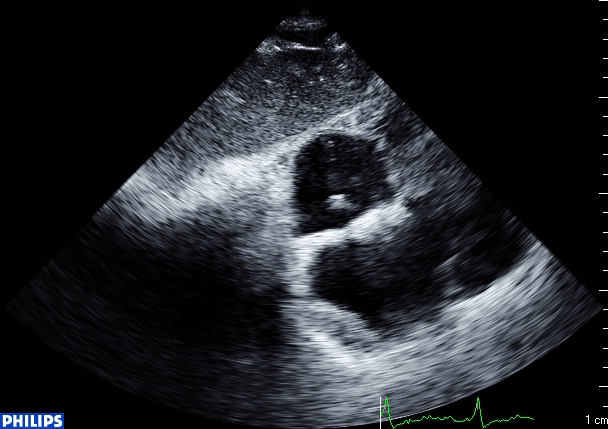

Coupe sous costale, septum inter auriculaire épaissi :

Et mon tout est une cardiopathie restrictive hospitalisée pour insuffisance cardiaque, et qui ressemble diablement aux petits copains du dessus! L’aspect granité, l’infiltration diffuse du septum, la dilatation auriculaire, tout y est, même l’épaississement du septum inter auriculaire!